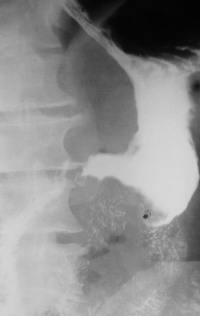

Achalazia cardiei